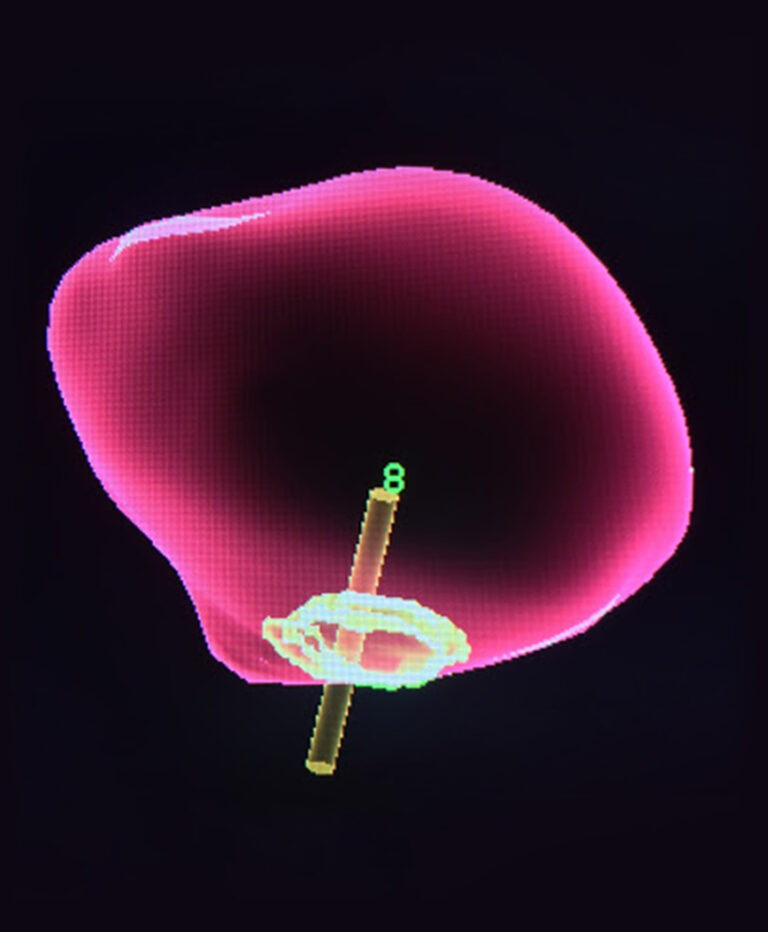

The process involves the use of 3T MRI imaging to look for potential cancers. The method can reveal the size and location of potential cancers and accurately determine how likely they are to be dangerous. For many men, this study can determine the presence or absence of cancer without the need for a needle biopsy—and for those who still need a biopsy, the MRI can be used to precisely target the area in question. This approach has proved to be a scientific breakthrough in the detection and treatment of prostate cancer, allowing for detailed visualization of the prostate gland, which is not possible with lower strength MRI and ultrasound alone. This highly specialized study requires highly specialized technology and expertise; the kind of expertise and technology you will find here at Insite Radiology.

Surveillance or treatment? This test provides answers.

Many prostate cancers require only regular monitoring. Low-grade, slow-growing cancers do not pose a health risk for many, many years. Other faster-growing prostate cancers require immediate treatment. The lack of complete information provided by the traditional combination of PSA testing and a biopsy may result in unnecessary types of treatments and side effects that could have been avoided. This state-of-the-art diagnostic tool has brought prostate cancer testing to the next level of accuracy, saving countless men from undergoing unnecessary treatments or overly invasive biopsy testing.